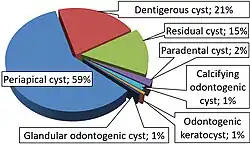

Periapical cysts comprise approximately 75% of the types of cysts found in the oral region. The ratio of individuals diagnosed with periapical cysts is 3:2 male to female, as well as individuals between 20 and 60 years old. Periapical cysts occur worldwide.

Types of Periapical cysts:

Apical: 70%

Lateral: 20%

Residual: 10%

- ^ Leandro Bezerra Borges; Francisco Vagnaldo Fechine; Mário Rogério Lima Mota; Fabrício Bitu Sousa; Ana Paula Negreiros Nunes Alves (2012). "Odontogenic lesions of the jaw: a clinical-pathological study of 461 cases". Revista Gaúcha de Odontologia. 60 (1).